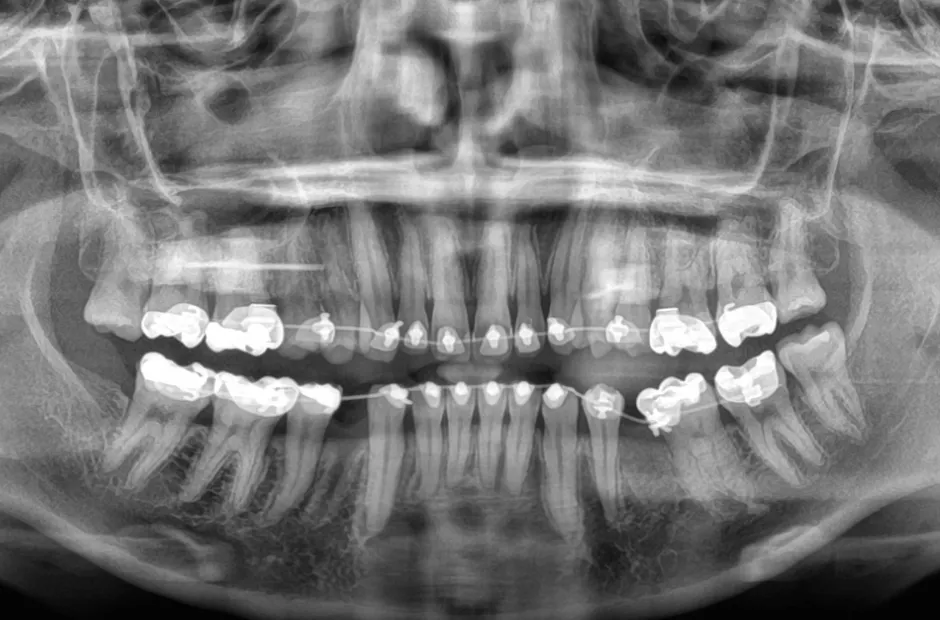

| 診断名・主訴 | 下顎前突、叢生 |

|---|---|

| 年齢・性別 | 23歳・女性 |

| 治療期間・回数 | 3年 |

| 治療に用いた主な装置 | 上顎5,5 下顎4,4 |

| 抜歯部位 | 舌側矯正 |

| 治療費 | 100万円(税抜) |

| リスク・副作用 | 装置による違和感・疼痛・歯肉退縮・歯根吸収・虫歯のリスクなど |

治療前

治療中